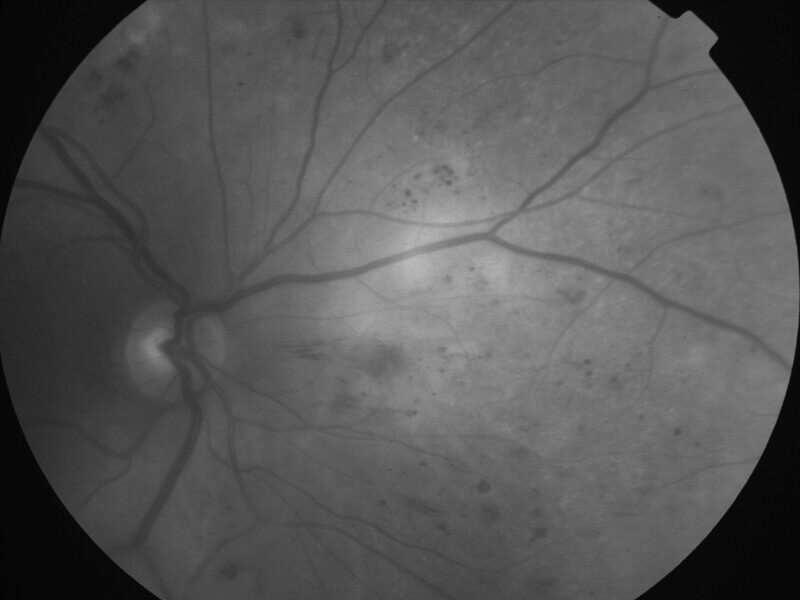

rétinopathie diabétique pré-proliférante